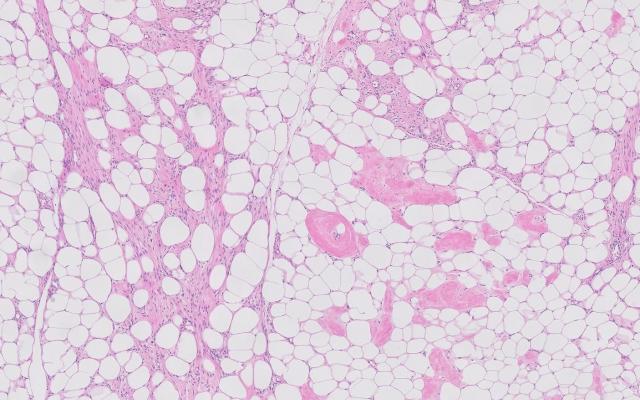

Actinomycosis van het kleine bekken